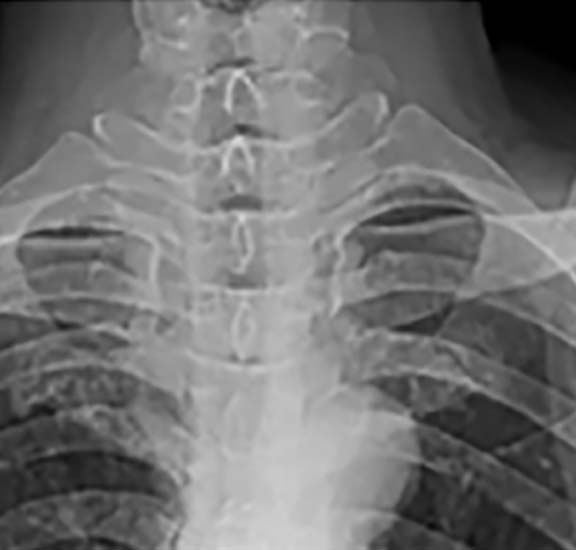

LUXAÇÃO ACROMIOCLAVICULAR

A luxação acromioclavicular consiste na perda de contato entre a clavícula e o acromio ( parte do osso da escapula). Isto ocorre em decorrência a um trauma na parte lateral do ombro. Com a luxação temos a impressão que a clavícula ascendeu. Além da deformidade o paciente apresenta uma dor intensa na região lateral do ombro. Para o diagnóstico utilizamos a radiografia. E com ela avaliamos o grau da luxação da clavícula. Para casos mais simples apenas uma tipoia por três semanas é utilizada no tratamento. Para os casos mais graves a cirurgia é indicada como o tratamento de escolha.